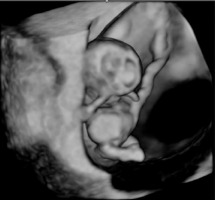

A thirty-three-year-old pregnant woman in her second pregnancy (the first pregnancy was unsuccessful – miscarriage at week 8 of pregnancy), visited a gynecologist for a routine check-up at week 12 of pregnancy, during which developmental disorders were found in the anterior chest cavity and abdominal walls. The woman was healthy, denied having chronic diseases, and was taking folic acid and vitamin preparations for pregnant women. The patient also denied the existence of any infections at an early stage of pregnancy. The woman was referred to the Laboratory of Prenatal Research, where, during prenatal ultrasound examination, the fetus was diagnosed with a complex defect of the skin and division of the body’s cavities in the form of pentalogy of Cantrell. The fetus was diagnosed with umbilical cord omphalocele (Figure 1), diaphragmatic hernia with diaphragmatic defect, sternal defect, ectopic heart and pericardial defect (Figures 2-3).